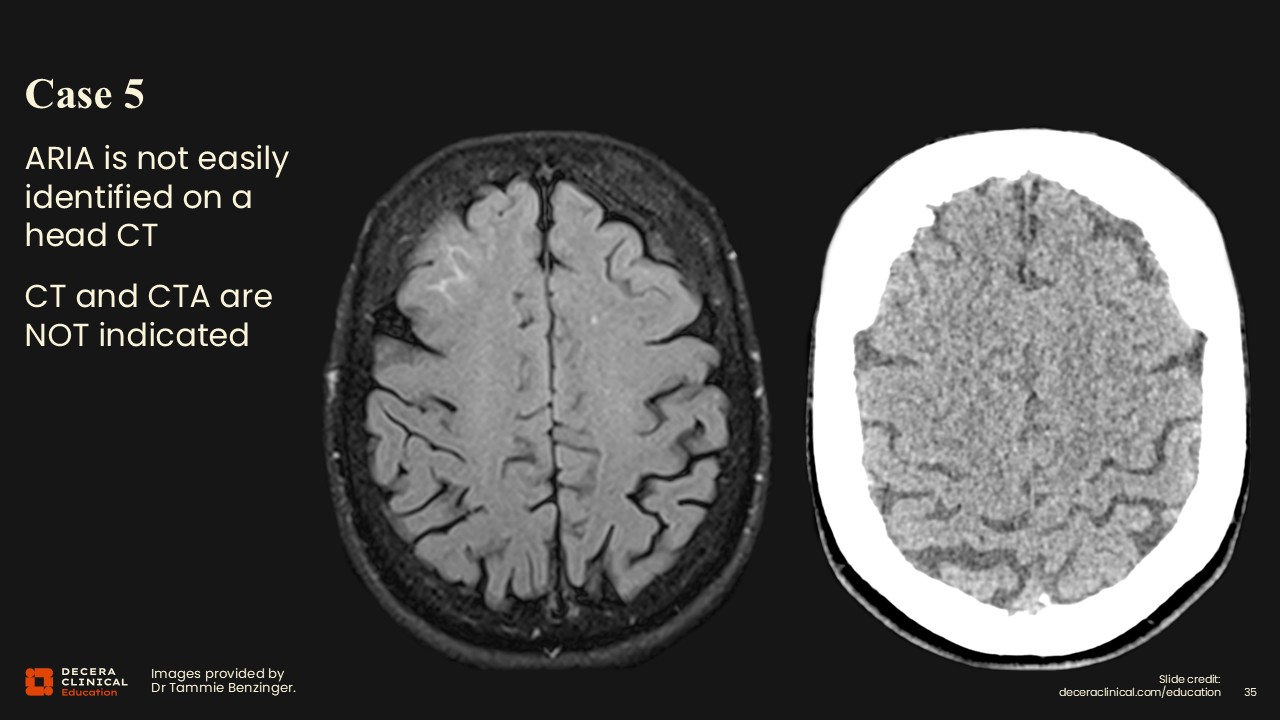

Case 5: ARIA Not Seen on Head CT and CTA

Dr Benzinger:

This is another example where a corresponding head CT failed to show the edema or hemorrhagic changes clearly. It is not well visualized, although you might think that it would be. This underscores that CT is not sensitive for typical ARIA findings and that MRI is preferred for detection and follow-up.

Case 5: Lessons Learned

This was another case where a couple of the findings were missed by the original radiologist. The edema was found but not identified as ARIA. This case illustrates that radiologists may correctly recognize edema but not connect it to ARIA in the context of ATT. Education and clear communication about a patient’s treatment status are essential so that radiologists can appropriately label and grade ARIA when it is present.